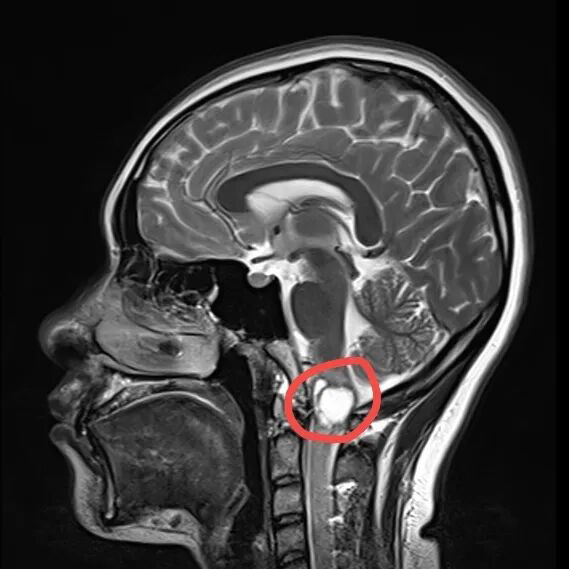

原来,孙女士家住安徽池州,两周前无明显诱因开始出现头痛症状,并伴有颈部不适,活动时颈痛加剧。当地医院颈椎MRI增强提示,延髓与颈髓交接区囊性占位,胶质瘤可能,建议转诊至上级医院。

孙女士入院后,成惠林主任对她进行了详细问诊。由于患者影像学检查提示,肿瘤位于延髓与颈髓交接区,位置深、毗邻生命中枢,手术难度极大,风险非常高。

位于延髓与颈髓交接区的巨大肿瘤

术后检查发现肿瘤已被完整切除